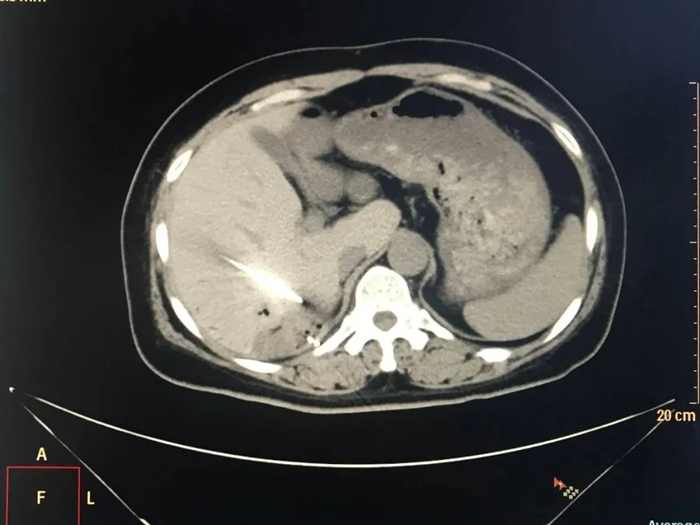

2023年4月,患者复查肝脏MRI显示病灶较前(2023年2月)增大。为了进一步控制患者病情,邢台市第九医院肿瘤内科一区团队会诊后,决定对她实施放射性粒子植入治疗。2023年5月,患者接受了CT引导下肝恶性肿瘤放射性粒子植入治疗,术后恢复良好。

放射性粒子植入术属于近程放疗,通常在超声或CT引导下进行,主要将125I粒子由细针直接穿刺至肿瘤并植入内部,通过其放射特性摧毁肿瘤。其优点在于125I粒子的射程较短、局部剂量高,便于把射线控制在肿瘤灶内,从而减少了射线对正常组织的损伤[1]

放射性粒子植入治疗凭借125I粒子对肿瘤细胞的持续杀伤作用,有效地控制了肿瘤的进展,且具有创伤小、并发症少、恢复快等优点,已成为肝癌常用的治疗方式之一。除了单独应用外,放射性粒子植入治疗还可联合其他治疗方式发挥出更大的优势。射频消融是肝癌最常用的局部治疗方法之一,放射性粒子植入治疗与其联合,可在肿瘤安全消融病灶范围不足的基础上辅以放射杀伤作用,扩大肿瘤坏死范围,提高肿瘤局部控制率[2]。放射性粒子植入治疗与消融治疗的联合应用,起到了取长补短的效果,能有效地控制残留病灶和改善预后,在转移性肝癌的治疗中发挥了独特的作用。